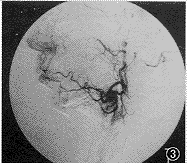

16例经颈外动脉主干造影,显示左侧出血14例,右侧出血2例,无双侧出血。均有不同程度的颌内动脉畸形扭曲、增粗、小动脉分支杂乱呈团状,有明显造影剂外溢及显影(图1),其中5例同侧面动脉畸形增粗,扭曲伴造影剂外溢(图2)。经明胶海绵超选择性栓塞颌内动脉、面动脉后,立即止血,取出后鼻孔填塞物未见出血(图3),再次造影无造影剂外溢。1例颌内动脉栓塞术后8个月再发同侧鼻出血,再次DSA检查为同侧面动脉出血,采用真丝微粒栓塞后止血,随访2年未再出血。诊断为颌内动脉畸形7例,面动脉畸形5例,颌内动脉分支小动脉瘤破裂2例,不明原因鼻出血2例。16例中栓塞1侧颌内动脉16例次,同时栓塞同侧面动脉5例次,再次栓塞同侧面动脉1例次。

图3 颌内动脉、面动脉栓塞后,血管受阻,达到立即止血效果